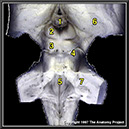

N1A5P7

21